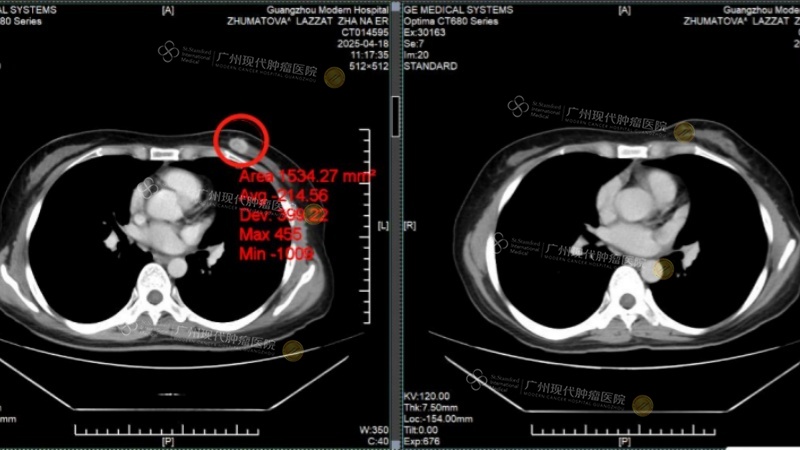

In April 2025, accompanied by her sister, LAZZAT arrived at our hospital and underwent a full-body examination. CT results showed a left breast mass approximately 2×1cm in size, multiple liver metastases with the largest nodule over 4cm in diameter, and liver function already impaired by the tumors.

[Breast Tumor: Before Treatment vs. After Treatment]

After two courses of treatment, LAZZAT's breast tumor was completely inactivated and had disappeared upon re-examination. The liver metastases had shrunk by more than half, her liver function indicators returned to normal, and tumor markers CEA and CA153 levels dropped significantly. Thanks to the meticulous care of the medical staff, her liver function improved, her feelings of fatigue and weakness markedly decreased, and she felt a long-lost sense of vitality.